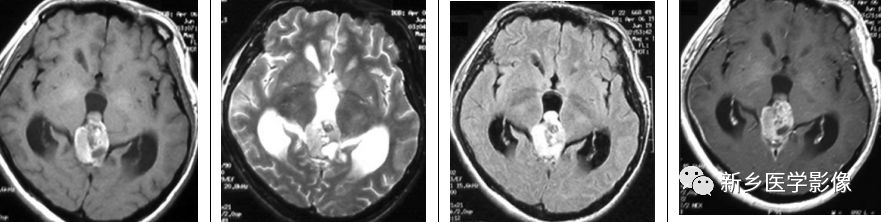

中分化松果体实质肿瘤为富核肿瘤。其可表现为轻度核不典型增生,偶尔可有核分裂。松果体细胞瘤玫瑰花结构缺失。与松果体母细胞瘤不同,中分化松果体实质肿瘤转移不常见。

横断位T1WI示松果体区高信号肿块,T2WI呈高信号,T21WI+FLAIR呈高信号,T1WI+C示部分强化。

松果体母细胞瘤

松果体母细胞瘤在男性及女性的发病率均等,主要见于10-20岁人群。其发病率约为松果体瘤的6倍。双侧视网膜母细胞瘤合并松果体母细胞瘤被称为三侧视网膜母细胞瘤。松果体母细胞瘤内可出现钙化。在磁共振上,其表现为T1WI低信号及T2WI高信号。病灶可见强化。

12岁儿童,矢状位T1WI示松果体区低信号肿块,横断位T2WI示一高信号肿块右份伴局灶性低信号,代表钙化,注意与病灶相关的脑积水;横断位及矢状位T1WI+C示明显强化肿块。